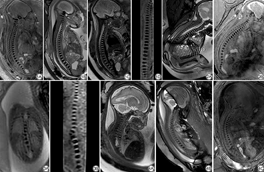

测量每个序列中图像对应ROI的信号值,并计算信号差值比*SI值。所有*SI值均符合正态分布,如表4所示。在胎儿颈椎显示方面,3D-T2*-FFE序列的*SI值高于2D序列,差异有统计学意义(P<0.05);各序列胎儿胸椎和腰骶椎的*SI值差异无统计学意义(P>0.05)。如图1到图4所示:在一些胎龄较大的胎儿图像中,三个序列都可以显示较好的胎儿脊柱图像(图1),但3D序列可通过后处理进行重建,可以提供更多的图像信息;2D BTFE序列受伪影影响较大,3D-T2*-FFE图像质量更佳(图2);图3和图4为胎儿脊柱异常的图像,显示椎体的3D序列明显优于其他两个2D序列。

本研究为国内外首次使用3D-T2*-FFE序列显示胎儿脊柱解剖及椎体畸形。既往的研究多局限于2D BTFE、磁敏感加权成像(susceptibility weighted imaging, SWI)等2D序列进行胎儿脊柱针对性扫描[13, 14]。本研究创新性地使用3D MRI对胎儿脊柱解剖显示及椎体畸形进行评估,研究结果表明3D-T2*-FFE序列对胎儿脊柱的显示效果良好,其扫描时间较短,可通过多种3D图像后处理方法,多方位显示胎儿脊柱图像,有利于胎儿脊柱畸形的早期诊断,具有较高的产前诊断价值。

在胚胎发育过程中,成骨细胞向内迁移,包围脊索,再经软骨化骨而形成椎体,若骨化中心未发育或融合失败,则可导致先天性脊柱侧弯和严重的脊柱畸形[9,15, 16, 17]。产前超声作为胎儿椎体畸形的重要检查方法,广泛应用于临床。但在如孕妇肥胖、肠道气体干扰、胎儿脊柱后位等情况下,超声不能清晰地显示脊柱的椎体,导致诊断困难[18, 19]。随着MRI快速成像序列的发展,2D SSH TSE序列和2D BTFE序列因其良好的图像质量而成为胎儿脊柱成像中最常用的序列[17]。胎儿在宫腔内的位置多变,脊柱轴相对弯曲,椎体结构较小,特别是胎儿的颈椎体积较小。以上两个序列都是2D成像因而导致了微小结构的显示效果相对较差,且不能通过3D后处理来进行多向显示[20, 21]。本研究结果显示,2D SSH TSE序列图像显示椎体边缘不清楚,颈椎表现差,对比度差。2D BTFE序列对椎体显示有良好的影响,但图像伪影可导致局部显示不清,影响图像质量。

由于缺乏氢质子,胎儿椎体的信号较低,与周围组织有明显的对比[22]。3D-T2*-FFE序列采用T2*加权成像,在传统的扫描时间中使用一个较小的翻转角度来实现较高的空间分辨率[23]。T2*-FFE序列优化了序列参数,改善了骨与周围软组织的对比[24, 25]。此外,3D成像序列采用无间距分割的扫描模式,避免了2D成像中信噪比的降低和图像对比度的变化,附加的信息收集使3D成像具有更高的空间分辨率和信噪比[26]。据报道,最常见的产前异常是胸椎(75.4%),其次是腰椎(60.0%)[27]。笔者推测,颈椎先天性椎体畸形的发生率相对较低,椎体体积较小,且对胎儿体位的影响较大,是导致颈椎畸形检出率较低的原因。有研究指出先天性脊柱侧凸与Klippel-Fiel综合征相关,脊柱检查应集中在颈部[28, 29]。在本研究中,主观图像质量评分分析显示,3D-T2*-FFE具有良好的颈椎图像质量,与2D SSH TSE和2D BTFE序列评分差异具有统计学意义。根据客观信号差值比*SI的计算和分析,2D BTFE和3D-T2*-FFE序列的对比优于2D SSH TSE序列,所以3D-T2*-FFE显示胎儿颈椎结构具有较高的诊断价值。

在MRI扫描过程中,胎儿的运动容易产生运动伪影,因此缩短扫描时间是减少运动对图像质量影响的关键。3D-T2*-FFE序列的扫描时间较短,单次扫描时间为12~17 s,可减少胎儿运动产生的运动伪影。另外,本扫描要求孕妇在扫描过程中屏住呼吸,防止呼吸产生的运动伪影,可以进一步提高图像质量,在短时间内提供良好的椎体图像信息。胎儿在子宫腔内的位置是可变的,部分胎儿脊柱轴是弯曲的,3D图像允许评估脊柱的完整解剖,这在2D成像中常常难以实现[30]。传统的2D序列图像可能只显示椎体的边缘部分,导致图像质量较差。通过多平面重建和曲线平面重建等后处理,3D-T2*-FFE可以多方位显示胎儿脊柱图像[31]。CAI等[32]报道了SWI对胎儿脊柱畸形具有良好的诊断价值,因为它提供了骨组织和软组织之间的高对比度。值得注意的是,SWI是一个2D序列,它也有2D序列如2D SSH TSE和2D BTFE的缺点。此外,该研究中的SWI序列要求进行两次屏气,每个周期为13 s,这对被检查的孕妇来说相对难以完成,因此可以认为3D-T2*-FFE序列在胎儿脊柱扫描中更为便利且具有优势。